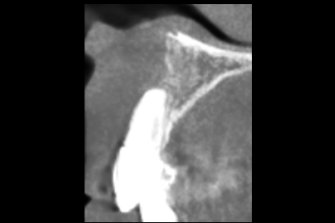

上唇の腫脹を認め、CT検査にて根尖部に嚢胞様透過像を認めた。左上の前歯が不自然に大きく噛み合わせが強くなっていたことがフレアアップの一因と考える。精密根管治療を行い、感染経路を遮断したのち歯根端切除術にて嚢胞を摘出した。

治療前